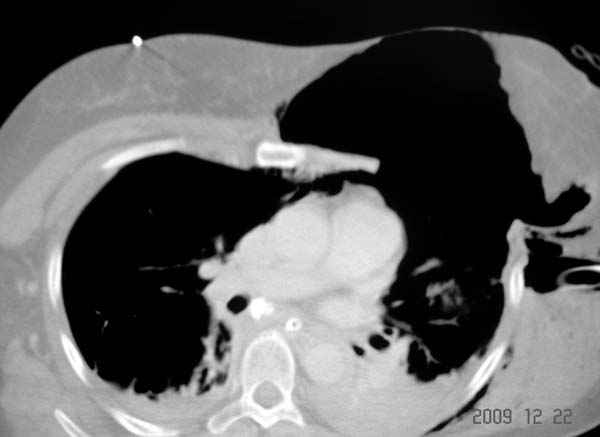

К нам поступила больная 56 лет после автоаварии в бессознательном состоянии, которая срочно заинтубирована в приемном отделении и сделаны необходимые исследования. Данные КТ и рентген показали перелом дистального бедра и Dissociation upper extremity - закрытый отрыв левой верхней конечности на уровне грудинно-ключичного сочленения и множественные переломы ребер.

На поверхности грудной клетки из-за полного разрыва грудной мышцы под кожей заметно биение сердца и след от ремня безопасности. Грудная клетка расширена из-за смещения верхней конечности вверх и латерально. Признаков васкулярного повреждения нет, и из-за отсутствия сознания не смогли определить наличия повреждения нервов.

Срочно в операционной наложен наружный фиксатор и травма хирургом поставлены трубки в плевральную полость.